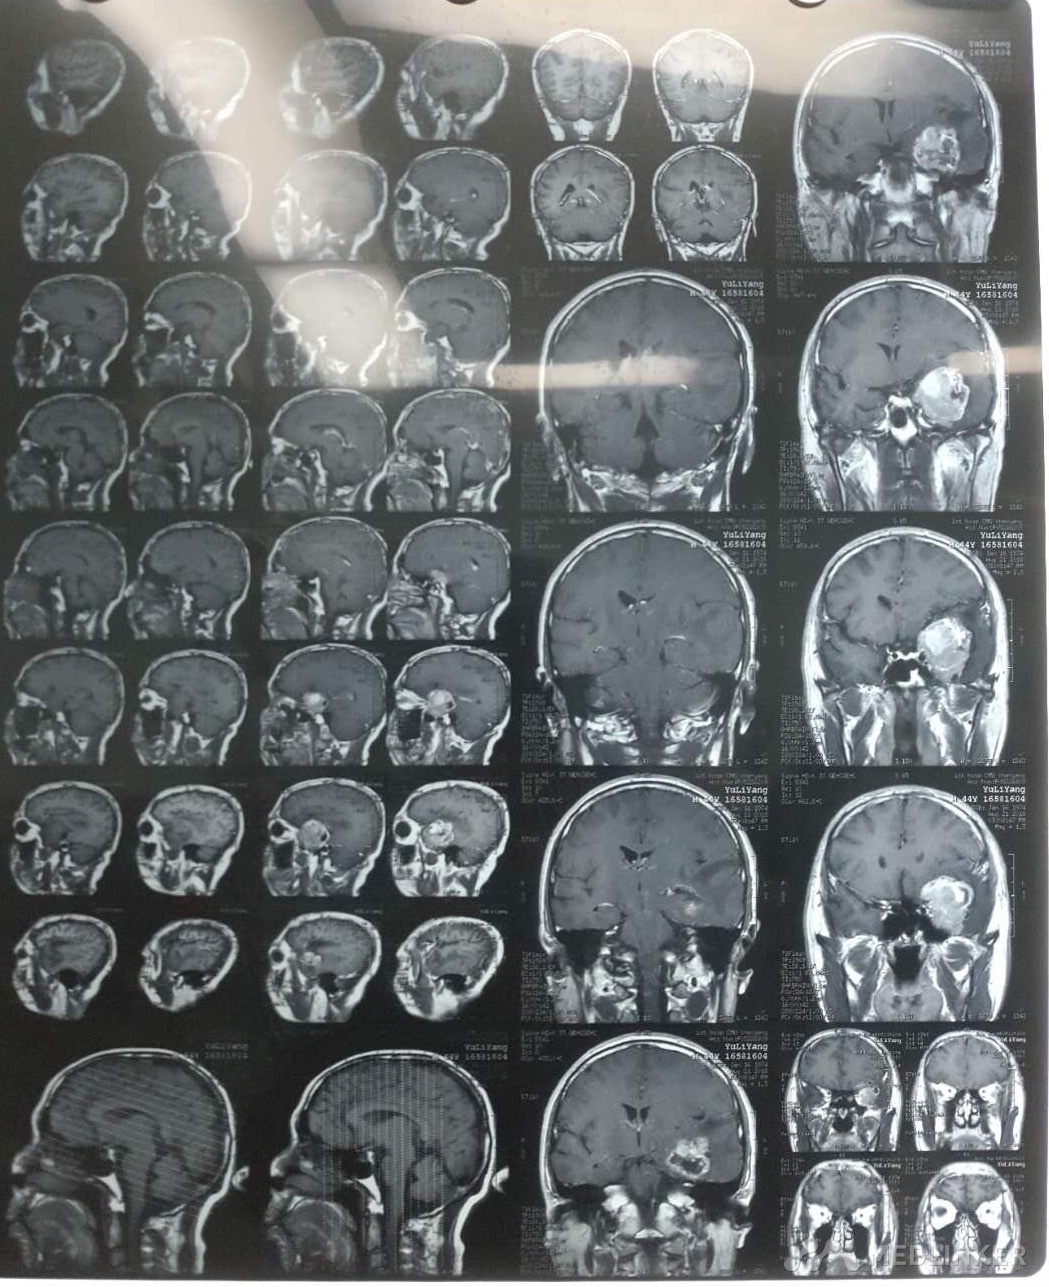

左侧颞叶占位

颞叶肿瘤

初步诊断:左侧颞叶占位,高血压,脑栓塞 确定诊断:左侧颞叶占位,高血压,脑栓塞 治疗:大脑深部病损切除术